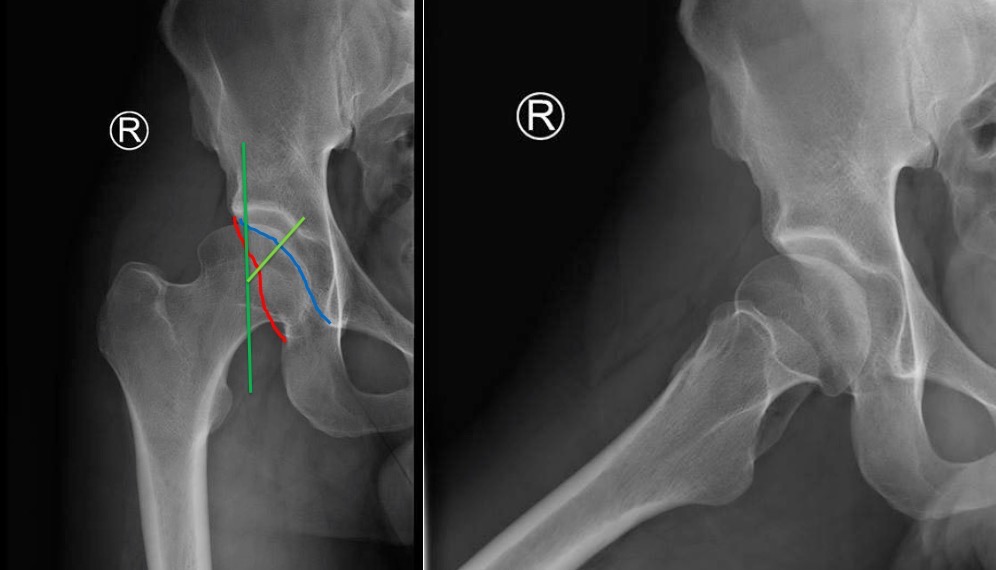

На представленном снимке (frog lateral) хорошо можно увидеть шейку и

головку, но для данной патологии требуется false profile view! Для

удобства приложил некоторые укладки: false profile и снимок с

нормальными параметрами сустава (синими указаны центр край угол). Здесь

имеется измененная и деформированная диспластическая форма головки, где

огромный размер, выходя за пределы вертлужной впадины, создает иллюзию

подвывиха. Очень узкая нагрузочная площадь и почти негативный

(center-edge angle of Wiberg), потому что вертикаль (зеленая) от центра

головки проходит с латеральной стороны. Контур передней стенки (синий)

показывает что покрывает головку мало, а задняя стенка (красная) больших

размеров доказывает что сустав развернут кпереди. Возможно за счет

укладки, на рентгене слева шейка вроде короткая.